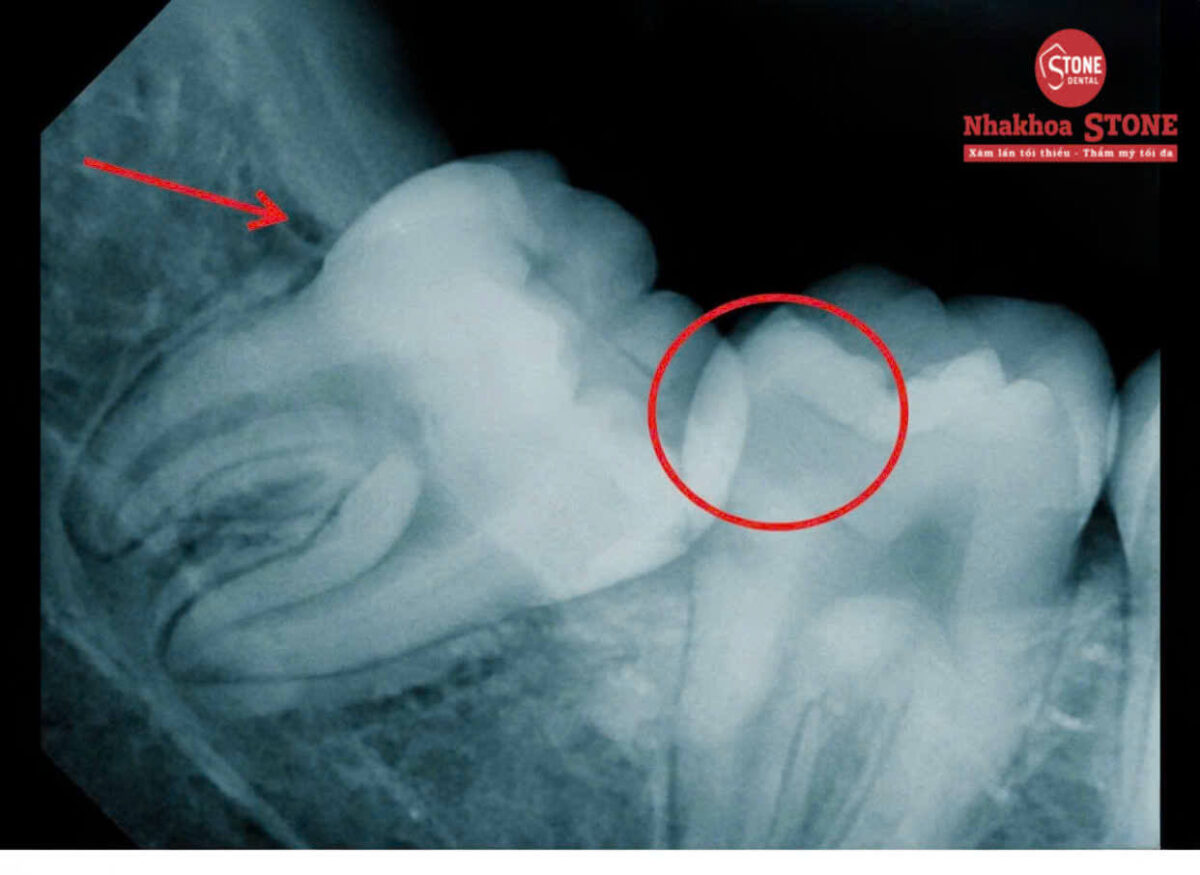

Răng Khôn Mọc Lệch Đâm Vào Răng Số 7: Nguy Hiểm Khôn Lường Và Cách Xử Lý

Bạn đang gặp tình trạng đau răng khôn, sưng nướu trong cùng hay ê buốt lan sang các răng lân cận? Đây rất có thể là dấu hiệu của răng khôn mọc lệch hoặc mọc ngầm gây biến chứng nguy hiểm. Hình ảnh X-quang thực tế dưới đây tại Nha khoa Stone sẽ giúp bạn … Đọc tiếp Răng Khôn Mọc Lệch Đâm Vào Răng Số 7: Nguy Hiểm Khôn Lường Và Cách Xử Lý